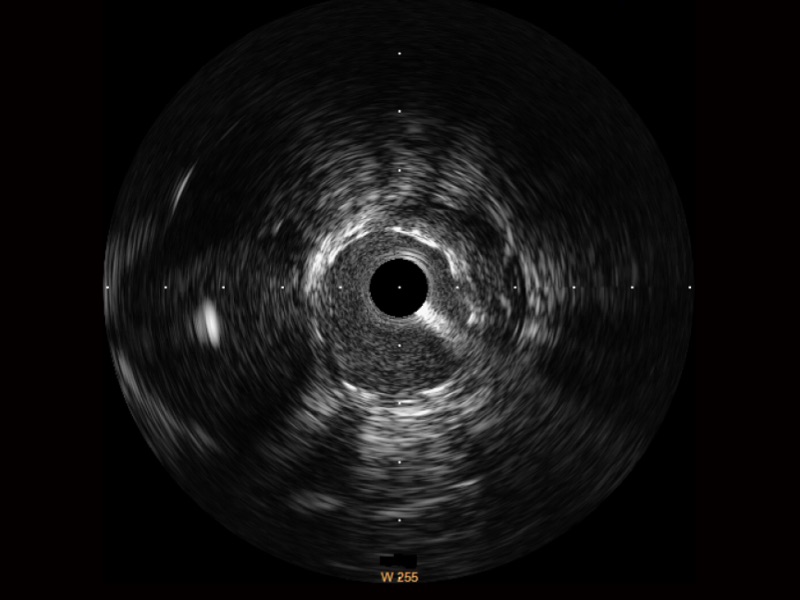

• 亚星官网宽频IVUS图像

• 传统IVUS图像

对比传统IVUS导管成像,亚星官网宽频IVUS图像的近场支架梁显影更细腻,远场中膜外血管仍清晰可辨,兼顾远中近,兼顾分辨力与穿透深度